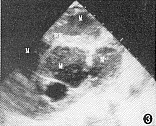

11例白血病肾浸润患儿中,9例为双肾浸润,其中双肾弥漫浸润4例,双肾多发结节浸润5例,9例中ALL 8例,ANLL 1例。CT平扫见弥漫浸润为两肾轮廓增大,肾包膜完整光滑,肾实质明显增厚,肾实质密度无异常,肾窦形态基本正常,增强后肾盂、肾盏显影轻度延迟。B超显示肾影增大、肾实质增厚的同时还显示回声均匀增强。 多发结节浸润的平扫CT见肾实质内多发的略高密度结节影,结节间可见线状低密度影将其分开(图1),结节突起使肾表面呈轻度分叶状。增强后肾实质内结节呈轻微强化,较平扫增长18 HU,密度均匀,结节内无低密度坏死区或出血,结节间见强化后受结节挤压变形的肾实质与集合系统,呈高密度分支状影(图2),肾实质强化程度较正常减低,在结节间自肾被膜下延伸至肾窦,肾盏变形拉长,肾盂显影明显延迟。B超显示肾实质回声增强,内见多发大小不等的结节(图3),中等强度回声,肾结构不清。化疗后复查,CT平扫显示双肾大小、形态基本恢复正常。本组2例呈单发结节浸润,均为ANLL。平扫CT见肾实质局限增厚,表面隆起,密度较正常肾实质略高,境界模糊(图4),增强后见肾实质内单发结节状影轻微强化,较平扫增长22HU,结节与正常肾实质间界限清楚(图5),肾被膜完整。B超显示肾实质内孤立中等强度回声结节(图6),肾结构受挤压变形。化疗后复查B超显示肾形态基本恢复正常。 本组化疗后5例复查CT与B超,显示肾轮廓明显缩小,肾实质厚度、密度或回声接近正常。11例患儿肝、脾均有不同程度增大。8例ALL患儿CT或B超检查同时显示胸腺浸润1例;肺及胸膜浸润4例;肾上腺浸润2例;腹膜后淋巴结浸润1例。3例ANLL患儿除肝、脾增大外CT或B超检查未显示其他脏器浸润。

图3 与图1同一病例。B超显示肾实质内多发中等强度均匀回声结节(M处),肾实质受挤压